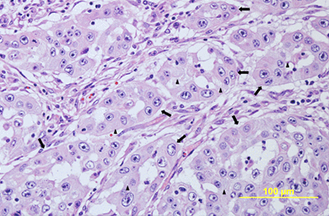

- Establishing a reproducible method for the culture of primary equine corneal cells